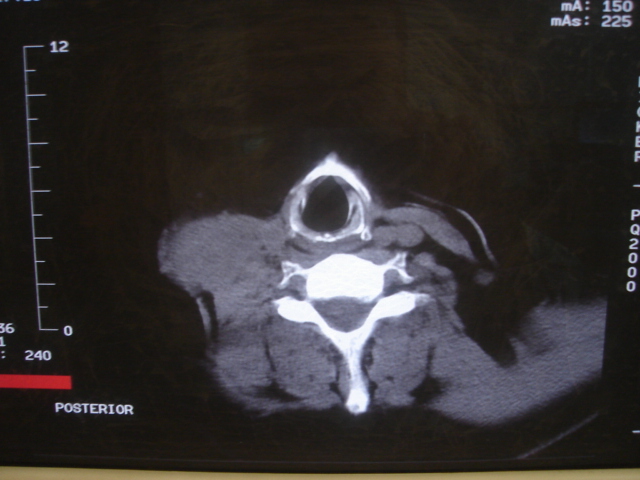

声门下区表面不光整,增厚呈局限性突起,未见局部浸润.

颈部多个淋巴结增大,结合甲状腺ca术后7年病史考虑转移。

1)右侧颈部淋巴结转移瘤。2)右侧声带新生物,性质待定;建议喉镜检查(活检)。

结合病史符合甲状腺ca术后颈部淋巴结转移